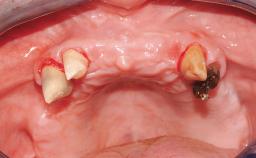

Immediate Loading of Six Implants in the Maxilla and Final Restoration with a Full-Arch CAD/CAM Zirconia FDP

A 63-year-old male patient was referred for a consultation and treatment of partial edentulism in the maxilla. The patient presented with residual anterior teeth and declined a partial removable prosthesis. He reported that the maxillary posterior teeth had been extracted due to mobility and periodontal disease two months before the consultation. The patient’s chief complaint was that his residual maxillary teeth were mobile and that he was unable to chew. The patient’s desire was a stable and comfortable fixed maxillary rehabilitation. The patient was a light smoker (fewer than 10 cigarettes/ day), and his medical history was without significant findings. He was not on any regular medication at the time of consultation. The extraoral examination revealed a normal physiognomy with a correct distribution of the facial thirds. The patient presented a low lip line, and the transition line between teeth and soft tissues was not exposed during a forced smile.

# of Implants 6

Soft Tissue Anatomy Intact Defective

Bone Volume Horizontally and vertically sufficient Horizontally deficient Deficient vertically or deficient vertically AND horizontally